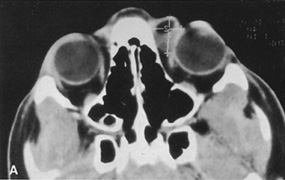

Valuable information about the nature and extent of an orbital pathologic process is provided by imaging studies such as computed tomography (CT) scan, magnetic resonance imaging (MRI), and orbital echography. Better spatial resolution, ready accessibility, and lower cost make CT the preferred choice for orbital imaging in most cases. Orbital fat provides a natural contrast between most adjacent orbital structures on CT scanning, and orbital bones are visualized well. Computed tomography is essential for evaluation of the orbital bones because they cannot be imaged with MRI. Direct coronal or sagittal images are important to identify the relationship of a lesion to the optic nerve so that the surgical approach can be planned to avoid traversing the optic nerve (Fig. 1).

Fig. 1. A. Axial CT scan demonstrating a large, well-encapsulated lesion in the orbital apex. Coronal (B) and sagittal (C) scans demonstrate that the mass lies inferior and medial to the optic nerve within the intraconal space. This information is useful in planning the surgical approach to the mass, which should avoid traversing the optic nerve.